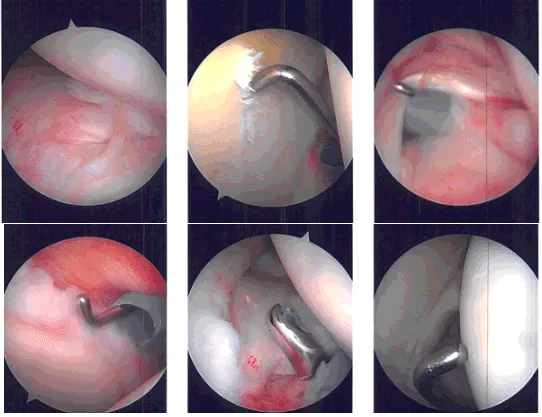

Intraoperative Arthroscopy Images

Entry to the anterior portal was made using a spinal needle through the rotator interval and cannula was inserted. Probe was used by examining the shoulder and found to have mild osteoarthritis, grade 1 to grade 2 osteoarthritis of the glenoid center.

There was partial tearing of the subscapularis, which was debrided. There was mild tendinitis of the biceps tendon and nothing was done for that. Complete rotator cuff tear was seen in the supraspinatus and Infraspinatus of the shoulder. There was fraying of the glenoid labrum, which was debrided using the shaver.

The examination of the shoulder was normal. The scope was entered through the anterior portal, findings. The scope was entered into the subacromial space.

Examination showed bursitis, which was debrided using the shaver. Big tear of the supraspinatus and infraspinatus was found. The tear was extending up to the biceps tendon.